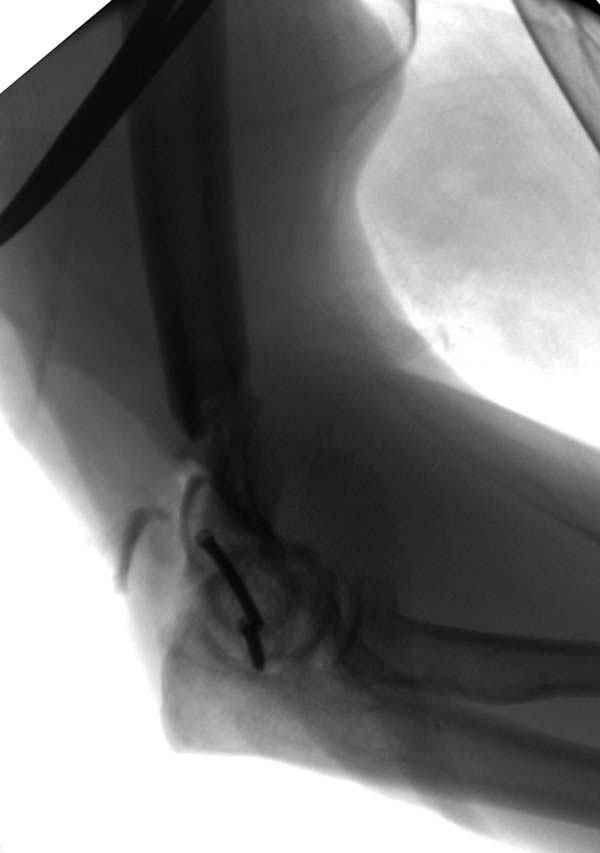

Примеры: первому более 15 лет фиксирован шурупом и tension band

technique, а второй перелом открытый больной 80 лет, после наружного

фиксатора в первом этапе и окончательная фиксация вторично. Третьий раз

внесуставная остеотомия...